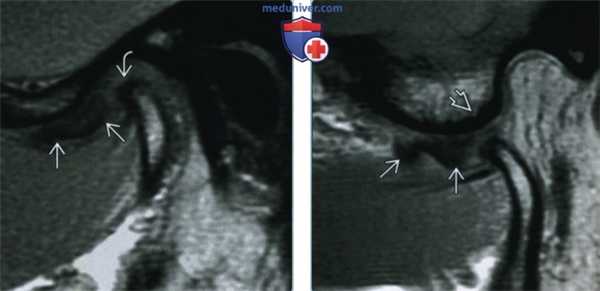

(Справа) В завершающей стадии закрывания рта до момента контакта зубов мыщелок находится в суставной ямке, а диск смещается вновь, обусловливая более мягкий щелчок закрытия рта. Задние связки диска растянуты и находятся в положении между 11 и 12 часами относительно мыщелка. (Слева) На косой сагиттальной PD МРТ (с закрытым ртом) визуализируется смещенный кпереди диск, задний пучок, которого находится на 10 часах относительно мыщелка. На более медиальном срезе диск занял нормальное положение. Следовательно, речь идет о частичном смещении диска.

(Справа) На косой сагиттальной PD МРТ (с открытым ртом) визуализируется промежуточная зона между мыщелком и гребнем суставного возвышения. В этом случае можно сделать заключение о частичном переднем смещении диска с редукцией. (Слева) На косом сагиттальном изображении центральных отделов ВНЧС с открытым ртом визуализируется вправившийся диск в этой зоне. При закрытом рте (изображения не продемонстрированы) диск был смещен кпереди.

(Справа) На косом сагиттальном изображении у этого же пациента (медиальнее по отношению к предыдущему срезу) визуализируется частично вправившийся диск. Задний пучок диска находится между мыщелком и суставным возвышением. Заключение: переднее смещение с частичной редукцией.